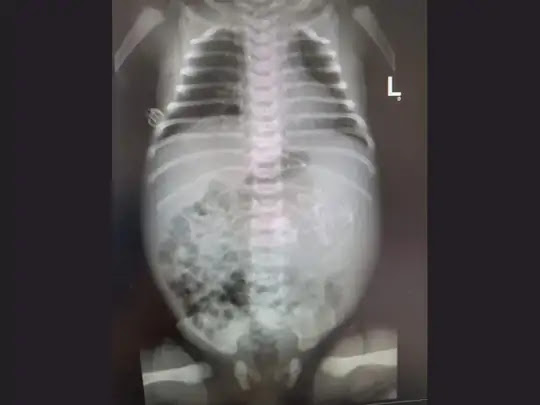

बच्ची का जन्म जुलाई के शुरुआती सप्ताह में अशदोद के असुता मेडिकल सेंटर में हुआ था। डॉक्टरों ने बताया कि गर्भावस्था के आखिरी हफ्तों में मां के अल्ट्रासाउंड के दौरान नवजात बच्ची का पेट अन्य बच्चों से बड़ा था. नवजात के जन्म के बाद डॉक्टरों ने उसका अल्ट्रासाउंड और एक्स-रे किया। परीक्षण रिपोर्ट ने पुष्टि की कि उसके पेट में एक से अधिक भ्रूण थे।

अस्सुता मेडिकल सेंटर में नियोनेटोलॉजी के निदेशक ओमर ग्लोबस ने कहा, “भ्रूण (Twin Inside Stomach) की पुष्टि के बाद हम चौंक गए थे। हमने चिकित्सा केंद्र के शीर्ष विशेषज्ञों के साथ मिलकर नवजात लड़की की सर्जरी की

और भ्रूण को उसके पेट से अलग किया। मुझे लगता है कि उसके एक से अधिक भ्रूण थे। हम इसकी जांच कर रहे हैं।

ओमर ने बताया कि भ्रूण पूरी तरह से विकसित नहीं हुए थे, लेकिन उसमें हड्डियां और दिल साफ देखे गए। सर्जरी सफल रही। मां और बच्चे को छुट्टी दे दी गई है।